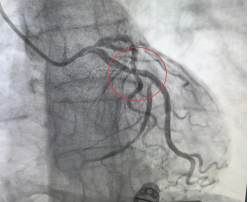

刘先生因“胸痛20天”入院,入院后进行了冠状动脉造影检查,发现其心脏的一支重要血管LCX(回旋支)中段存在弥漫性狭窄,最重处狭窄约90%,确诊为冠心病。随后,内科一病区医生团队为患者实施了冠状动脉支架植入术,术后胸痛症状明显缓解,恢复良好,生活质量显著提升。

(术前) (术后)